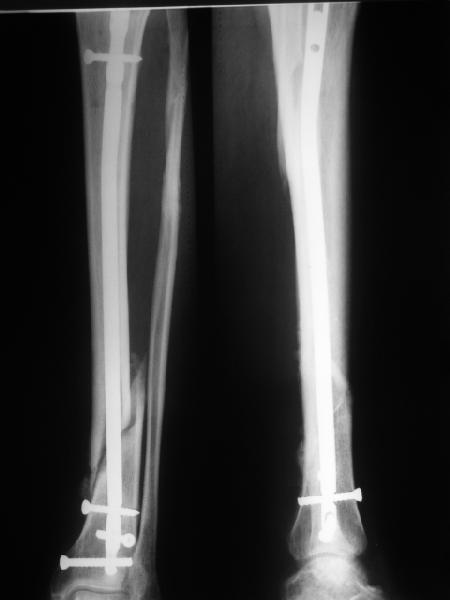

[Ortho] неправильно фиксированный перелом

В приложении картинка пациента со сломанным внизу гвоздем. Начал

лечение в другом учреждении. Еще и адвокат к тому же.

Динамизировали через 8 недель, а оно поползло больше, чем хотелось бы.